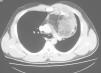

Radiología Casos en imagen 2

Casos en imagen 2

Case 2

J. Cubero Carraleroa, JM. Abadal Villayandrea, V. Guadaño Salvadoresa

a Servicio de Radiodiagnóstico. Hospital Severo Ochoa. Madrid. España.